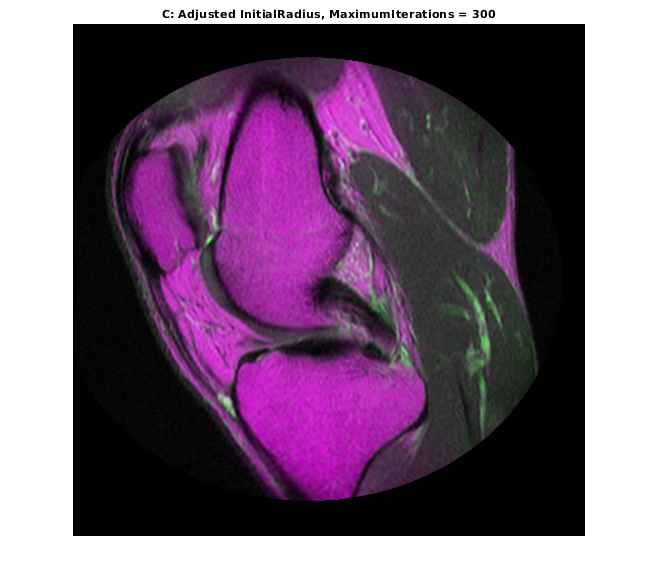

optimizer.MaximumIterations = 300; movingRegisteredAdjustedInitialRadius300 = imregister(moving,fixed,'affine',optimizer,metric); imshowpair(movingRegisteredAdjustedInitialRadius300,fixed) title('C: Adjusted InitialRadius, MaximumIterations = 300')

Дальнейшее совершенствование регистрации было достигнуто путем многократного использования оптимизатора InitialRadius, сходящего с предыдущей регистрации и позволяющего оптимизатор взять большое количество итераций.